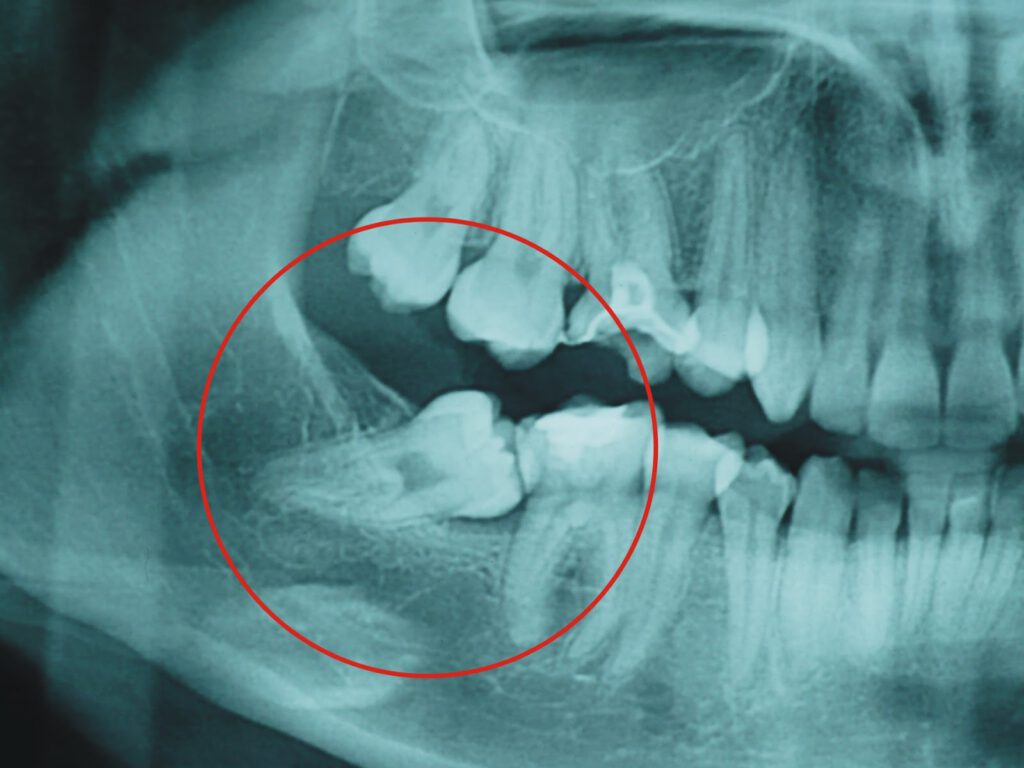

Los cordales, muelas del juicio o terceros molares, son los cuatro molares que se forman en la parte posterior del maxilar o la mandíbula.

La dentición de un adulto normalmente se compone de 28 dientes; 32 en el caso de que se formen las cuatro muelas del juicio.

Las muelas del juicio suelen salir entre los 16 y los 22 años; si bien hay ocasiones en las que pueden salir antes o después, o no hacerlo nunca.

Muchas personas tienen las muelas del juicio impactadas o retenidas; lo que les puede producir:

• Daño de los dientes adyacentes o del hueso de los maxilares

• Formación de quistes alrededor de las muelas del juicio

Por lo general, le solicitará una radiografía panorámica u ortopantomografía para valorar su caso; y en caso de ser necesario complementar el estudio podría solicitarle un CBCT (Tomografía Computarizada de Haz Cónico).